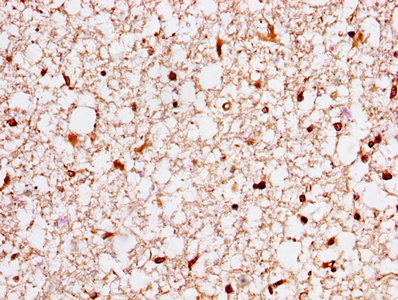

Immunohistochemistry of paraffin-embedded human prostate tissue using CSB-PA02174A0Rb at dilution of 1:20